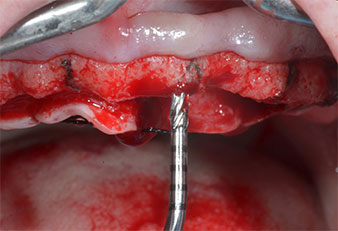

Uno strumento piezoelettrico (Piezomed I1) a forma di fiamma, rivestito in diamante, è stato usato per contrassegnare le posizioni dell'impianto e per eseguire una preparazione pilota (Fig. 3). Si è prestato attenzione a utilizzare un movimento verticale ascendente e discendente, con potenza ridotta, irrigazione completa e bassa pressione (inferiore a 300 g). Successivamente è stato applicato uno strumento pilota (Piezomed I2A/I2P) per l'ingrandimento iniziale delle sedi dell'impianto del diametro di 2 mm (Fig. 4), seguito da un inserto da 3 mm (Fig. 5).

Strumento marcatore a ultrasuoni Piezomed

Fig. 3: la preparazione con lo strumento marcatore a ultrasuoni Piezomed I1 viene eseguita in un movimento verticale ascendente e discendente, parallelo all'asse longitudinale della parte lavorante.